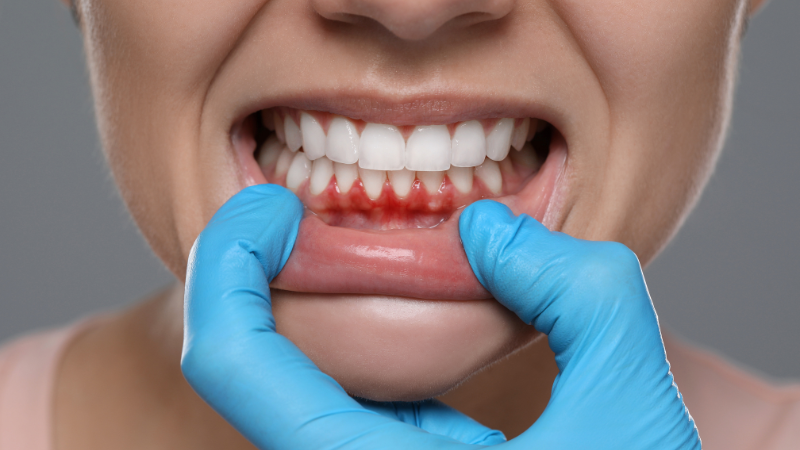

① 歯周病による歯茎の腫れ

歯茎の腫れとして最も多く見られる原因が、歯周病です。

歯周病は、歯と歯茎の境目に溜まったプラーク(歯垢)に潜む細菌が増殖し、歯茎の組織に炎症を引き起こすことで発症します。

初期段階(歯肉炎)では「歯茎が少し赤い」「ブラッシング時に出血する」程度の症状ですが、進行するにつれて歯茎が大きく腫れ、痛みを伴うこともあります。

歯周病は自覚症状が現れにくい病気で、気づかないうちに進行してしまう可能性があるため、定期的な歯科検診が非常に重要です。